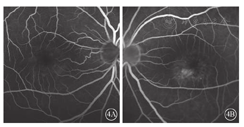

患者女,26岁。因左眼视物变形1个月于2018年9月17日到上海和平眼科医院就诊。患者3年前于外院诊断为"双眼闭角型青光眼",并行双眼YAG激光虹膜周边切除手术。否认家族遗传病史,其母视力及眼底检查正常,其父视力正常。10多岁时发现夜盲。患者一般情况良好。眼科检查:右眼视力1.0;左眼视力0.6,矫正不能提高。双眼屈光度均为+0.5 DS。右眼、左眼眼压分别为30、28 mmHg (1 mmHg=0.133 kPa)。双眼眼轴长度均为21 mm。双眼眼前节正常,前房浅,上方虹膜周切口通畅。晶状体透明,玻璃体不混浊。双眼视盘边界清楚,C/D为0.8;视网膜血管未见明显异常。双眼视网膜后极部不均匀黄白色物质沉积,黄斑中心凹反光消失(图1)。频域OCT (SD-OCT)检查,右眼内核层层间劈裂,外界膜下椭圆体带、光感受器外节大量强反射物质沉积,RPE/Bruch膜上锥形强反射物质沉积,两层强反射之间有弱反射暗区(空腔);左眼黄斑中心凹RPE下强反射隆起,Bruch膜断裂(图2)。OCT血管成像(OCTA)检查,右眼脉络膜毛细血管层大片血流信号遮蔽成暗区,其内及边缘见小片状非血流信号团;左眼无脉管层暗区内见线团状异常血流信号团(图3)。FFA检查,右眼黄斑中心凹旁斑片状强荧光,晚期染色;左眼晚期黄斑鼻下方三角形强荧光素渗漏(图4)。FAF检查,双眼后极部斑点状环形强荧光,累及颞侧及下方视网膜(图5)。EOG检查,双眼光峰值降低或消失,右眼、左眼Arden比值分别为1.2、1.1。诊断:双眼常染色体隐性卵黄样黄斑营养不良(ARB );左眼脉络膜新生血管(CNV)。患者于复旦大学附属眼耳鼻喉科医院行基因检测,提示BEST1基因杂合突变,突变位点c.140G> A,氨基酸变化p.R47H。给予双眼降眼压药物治疗;左眼玻璃体腔注射雷珠单抗治疗,每月1次,连续3次。左眼第1次注射后,患者诉视物变形症状消失;视力1.0。随访至今无变化。

BEST1基因相关ARB为少见眼底病变,其起源于RPE基底外侧的BEST1基因发生突变,BEST1基因失去功能,导致RPE及视网膜功能障碍[1,2,3,4,5]。该病好发于儿童及年青人,性别无异。双眼或单眼中心视力下降是主要症状。眼底检查可见黄斑区多个位于视网膜下的黄白色沉着物,可以累及血管弓周围甚至中周部视网膜。病变在FAF检查下显示更为清楚,且数量更多。OCT检查可见视网膜内囊样水肿或黄斑视网膜脱离;RPE上或内见到强反射团块即为黄白色沉着物;视网膜外层椭圆体带可能断裂,RPE也可出现萎缩。OCTA检查可见脉络膜毛细血管层血流信号被卵黄样物质遮蔽形成暗区,在无脉管层清晰显示暗区内线团状的异常血流信号团,即CNV。而FFA上因卵黄样物质染色等原因不易发现新生血管渗漏。这提示,对于ARB患者,OCTA检查更容易清楚发现CNV病灶。既往研究发现,与显性卵黄样黄斑营养不良(BEST病)的正常ERG表现有所不同,ARB患者可能有视锥、视杆细胞振幅降低或潜伏期延长[6]。但本例患者因客观原因未能行ERG检查。其EOG检查可见光峰值降低或消失。本例患者临床及多模式影像检查均符合ARB的眼底特征。